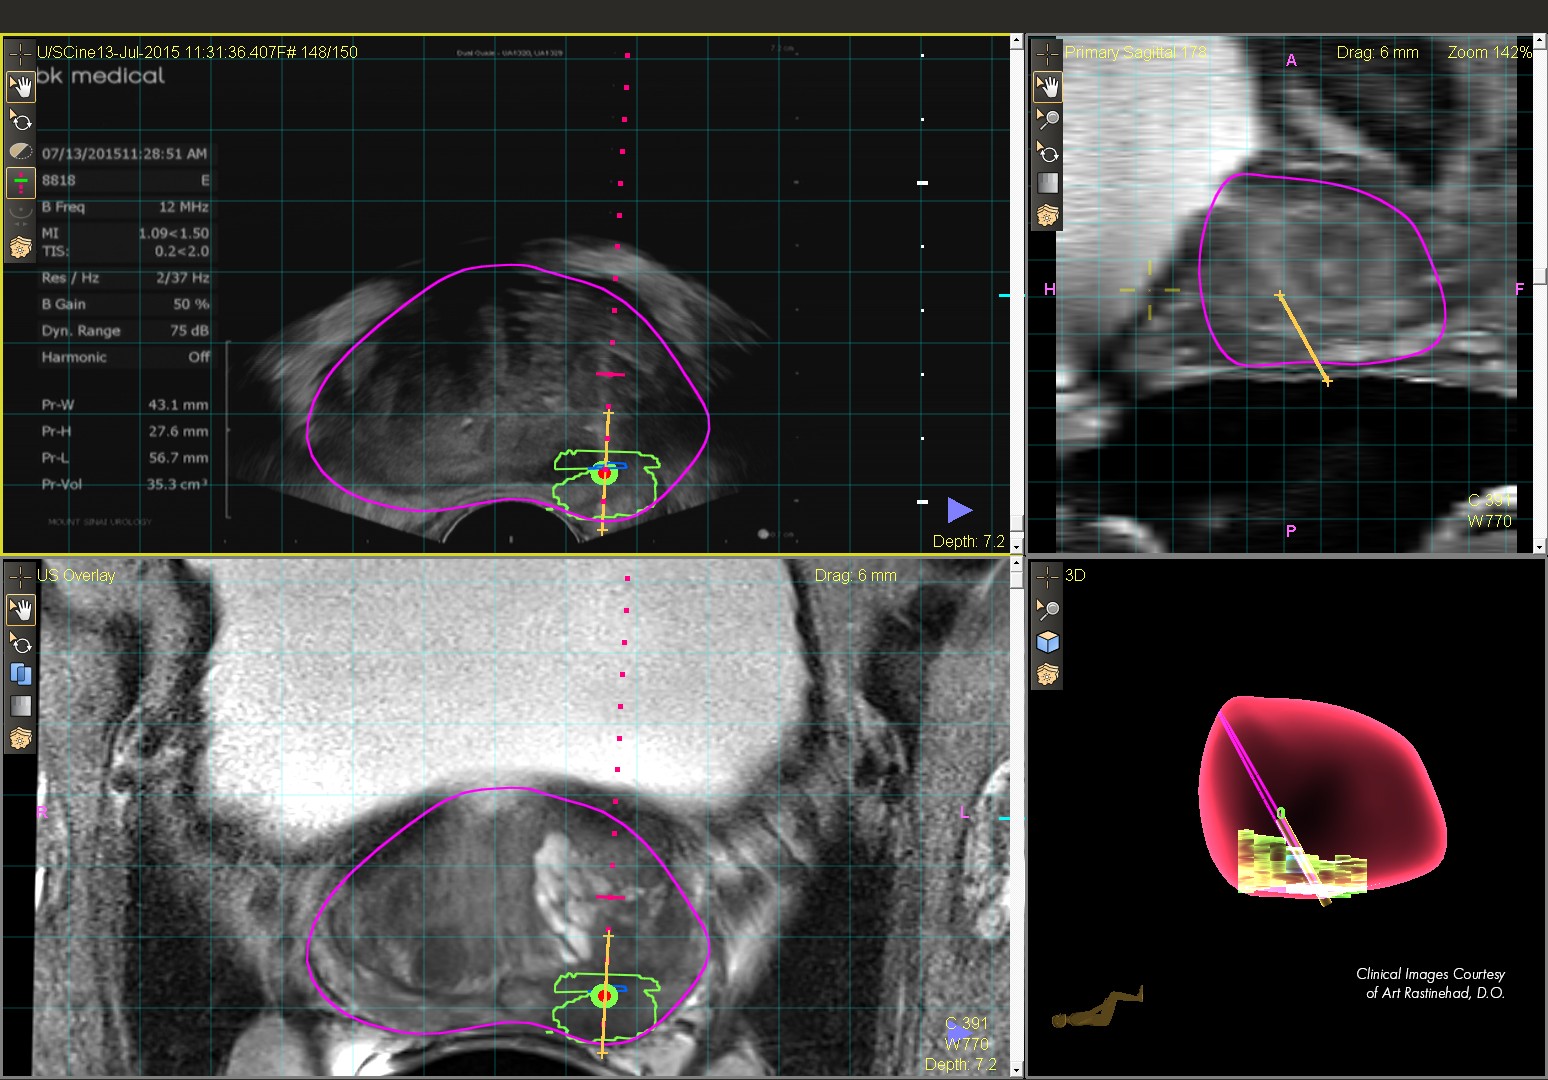

Targeted MR/ultrasound biopsy is poised to become a new standard in prostate care. This technique fuses pre-biopsy MR images of the prostate with ultrasound guided biopsy images in real time, for excellent delineation of the prostate and suspicious lesions, as well as clear visualization of the biopsy needle.

UroNav helps to visualize targeted MR/Ultrasound biopsy procedures with a simple workflow and robust features.